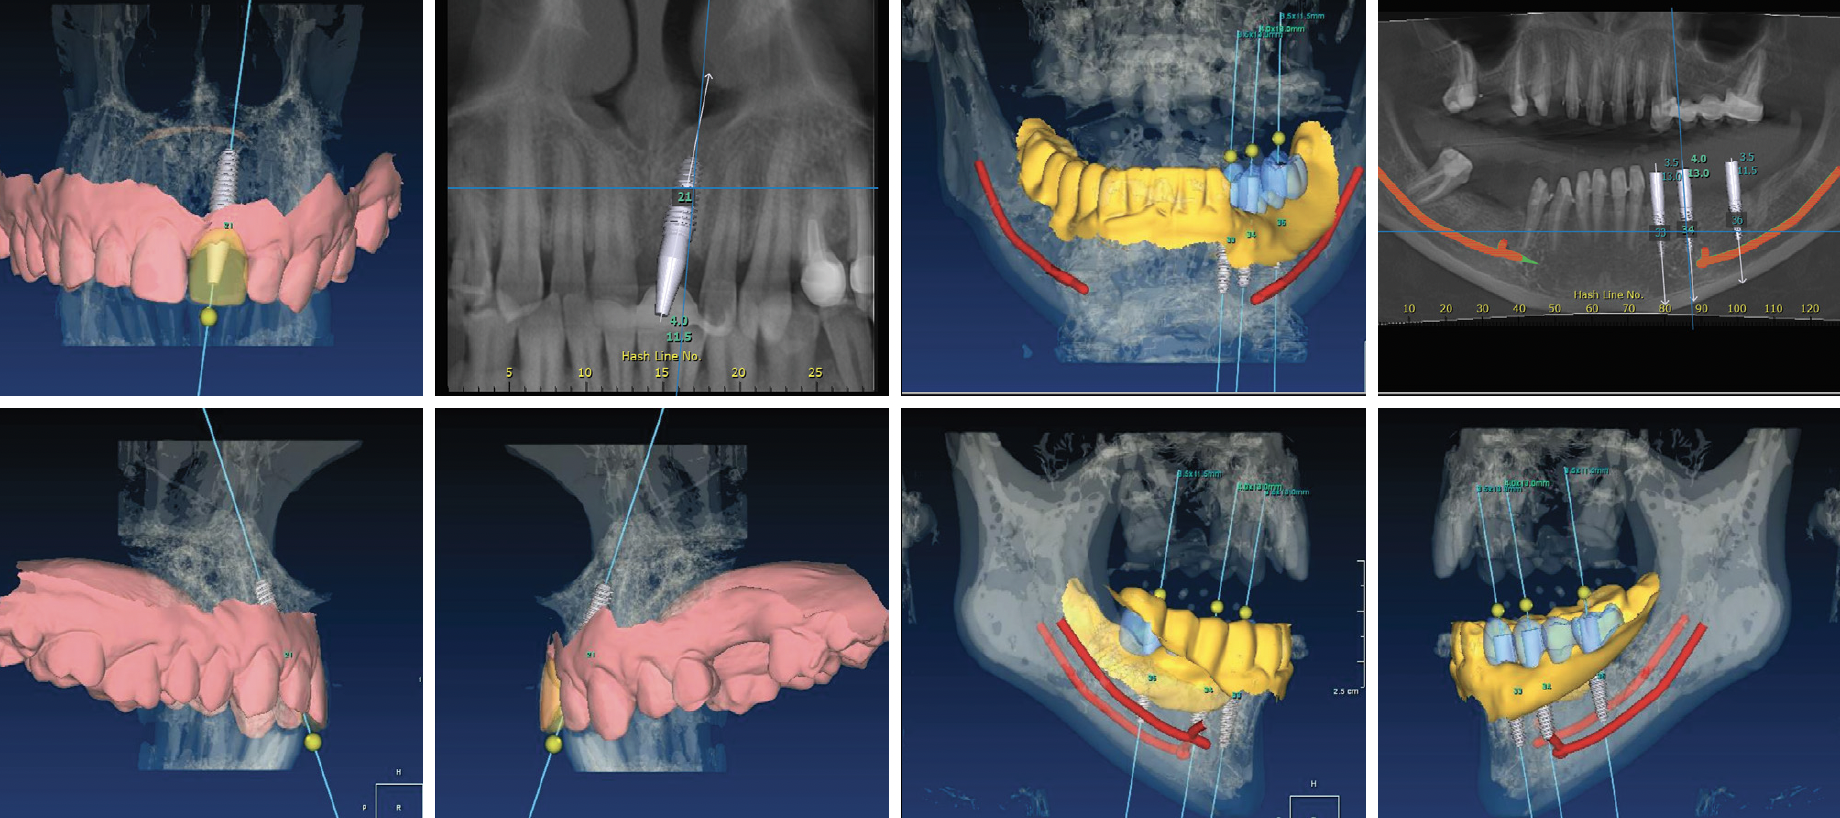

În acest sens, tehnologia permite medicului ca, preoperator, să evalueze toate datele, să stabilească un plan de tratament corect prin alegerea celui mai bun tip de implant și să stabilească poziția finală a implantului endoosos (Fig. 7.5.1). După realizarea acestui plan virtual, se va concepe un ghid chirurgical care să permită medicului preparea cavităților și aplicarea implantului în poziția dorită (Fig. 7.5.2). Ghidul chirurgical are aspectul unei gutiere care se așează pe dinții dumneavoastră iar la nivelul zonei edentate prezintă unul sau mai multe cilindre cu rol de a direcționa secvența de forare (Fig. 7.5.3).

Figura 7.5.1 Planningul virtual chirurgical. Stabilirea viitoarelor poziţii ale implanturilor